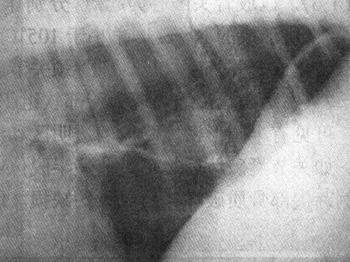

2)脱位 对半脱位和深在性脱位,临床诊断较为困难,须进行X线检查。全脱位的X线表现为关节内两骨端的关节面对应关系完全脱离(图1-2)。半脱位的X线表现是相对应的关节面部分脱离,失去正常相互平行的弧度和间隙。先天性脱位多见于膝关节,X线显示股内踝关节面平坦,外滑车发育不良等。

图1-2 猫左膝关节脱位合并右胫骨近端骨折

侧位显示左膝关节正常位置发生改变,左胫骨向前移位。右胫骨近端骨折、移位重迭,骨干有骨裂